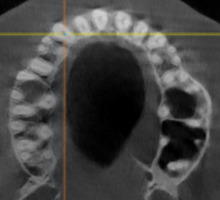

При анализе и описании компьютерной конусно-лучевой томографии (рис. 2а-г) была выявлена генерализованная первичная дегисценция вестибулярной пластинки кости от 1/2 до 3/4 длины корней зубов, зубной ряд целостный, все зубы витальны, кариозных поражений нет. Тип кости 1-2 (Lechkolm и Zarb, 1983), первичная дегисценция вестибулярной костной пластинки превышает пределы возрастной атрофии.

Через 12 месяцев (рис. 7а-г) на срезах компьютерной томограммы 11-ый и 13-ый зубы находятся в костной ткани, при этом костные пики и перегородки укрепились, объем их увеличился; вестибулярно заметен объем костной массы, предположительно компактной формации, исходя из электронной плотности участка. Этим объясняется отсутствие рецидива при лечении рецессии десны как в случае применения аутотрансплантата, также и ТМО (dura mater).